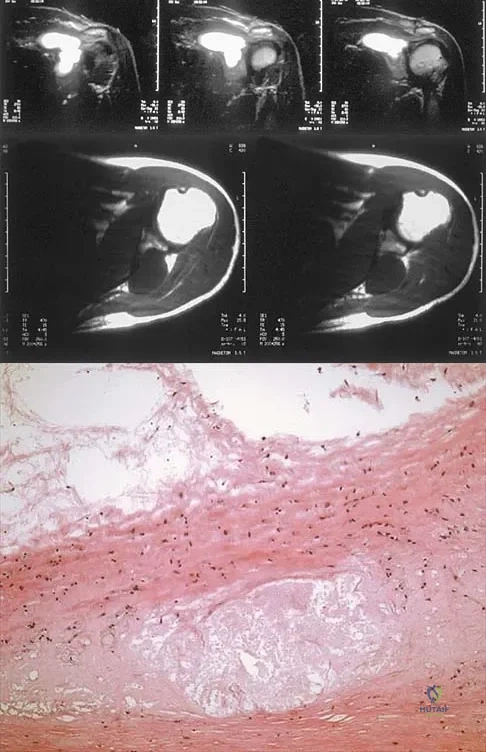

A 37-year-old man has left shoulder pain and weakness. Coronal T1- and axial T2-weighted MRI scans are shown in Figures 17a and 17b. The biopsy specimen is shown in Figure 17c. What is the most likely diagnosis?

Explanation